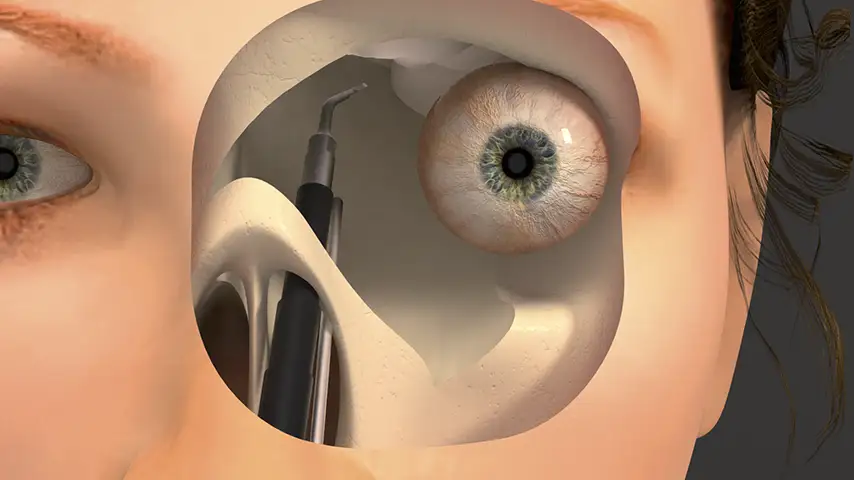

in Orbital Surgery

Osteotomies of orbital bones

Details

Minimized risk of CSF leaks and orbital damage. Improved aesthetics, preservation of fixation materials, and avoidance of substitutes through precise cutting. Reduced heat enhances ossification with implants.

Orbital

decompression

Optic nerve decompression

Details